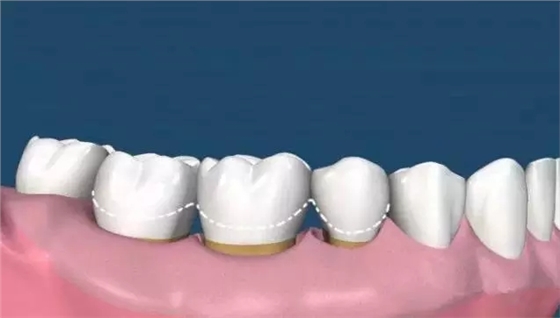

(圖中線條部位為正常牙齦位置,牙齒不光滑的表面布滿牙結(jié)石)

超聲波洗牙清潔掉牙齒表面上的菌斑和牙結(jié)石,牙齒根部的結(jié)石還未去除,且牙齦依然還會存在紅腫的情況,所以需要繼續(xù)齦下刮治治療。

這時候很多人會發(fā)現(xiàn),齦上潔治和齦下刮治之后,很多人會發(fā)現(xiàn)牙根暴露在外面,而且牙縫明顯。

這是因為洗牙前牙齒的縫隙是因為那些縫隙里面填滿了牙結(jié)石,舌頭舔上去感覺不到,當(dāng)結(jié)石清除后,縫隙就會顯露出來。

而牙結(jié)石的堆積導(dǎo)致牙齦的退縮、牙根的暴露和牙槽骨的吸收,牙槽骨吸收以后是沒辦法恢復(fù)的,所以等到很嚴(yán)重才來看牙醫(yī)的時候,問題也許無法彌補(bǔ)了。